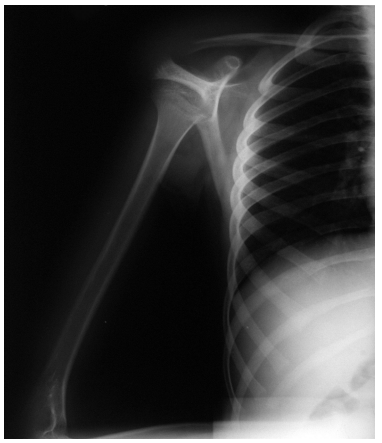

| Figure 1a: standard x-ray carried-out in the emergency room |

| Figure 1b:standard x-ray carried-out in the emergency room |

Male, 7 years and 9 months old; fell from the dad’s motorbike hitting on the floor the right shoulder. Reached the emergency room immediately after the trauma. At the clinical examination presented swelling and deep pain at the pressure on the coracoid and all over the shoulder; the motility was good but it reawaken/stirred pain in particular in abduction. The standard x-ray carried-out in the emergency room suspecting a fracture of the clavicle or humerus (figureure 1 a-b) underlined a light discontinuity at the base of the right coracoid, centering of the humeral head and continuity of the acromio-clavicular joint. Are requested the specific and comparative projections of the left shoulder (figureure 2 a-b) that highlights the separation of the coracoid base with small compound fracture. Is decided for a conservative treatment by applying Desault bandage for 25 days. At the removal, the clinic examination shows light pain at the mobilization of the shoulder and at the pressure on the coracoid. The radiographic exam points out good consolidation of the fracture and his realignment (figureure 3 a-b). At the clinic follow-up after 20 days after the removal of the bandage, the patient does not complain any pain and presents a complete motility of the shoulder.